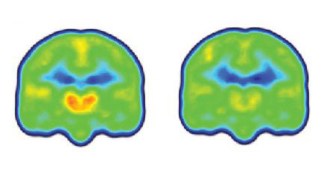

11. Neuroscience

Shots of brain cells restore learning, memory in rats

Scientists healed damage caused to rats’ brains from radiation by injecting cells that replenish the insulation on neurons.